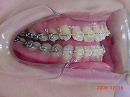

初診日 18歳7か月 女子

見えにくい矯正装置で骨のたわみを治療します。

通常の矯正装置でそれぞれの歯の位置を治療します。

MEAW(マルチループ)を利用して仕上げていきます。

終了日 20歳1か月(治療期間2年1か月)